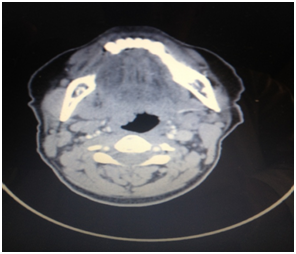

A CT scan of the neck following IV administration of contrast material was performed and showed that there is evidence of relatively large 5*3cm hypodense parapharyngeal mass lesion medial to the deep portion of the right parotid gland reaching the level of the right side of the nasopharynx and oropharynx causing compression of the nasopharynx airway with narrowing of its lumen and extending to reach the base of the tongue and right side of the oropharynx causing compression and narrowing of its lumen.

Figure 3 Tumor compressing the oropharynx.

Figure 4 Tumor compressing the nasopharynx.